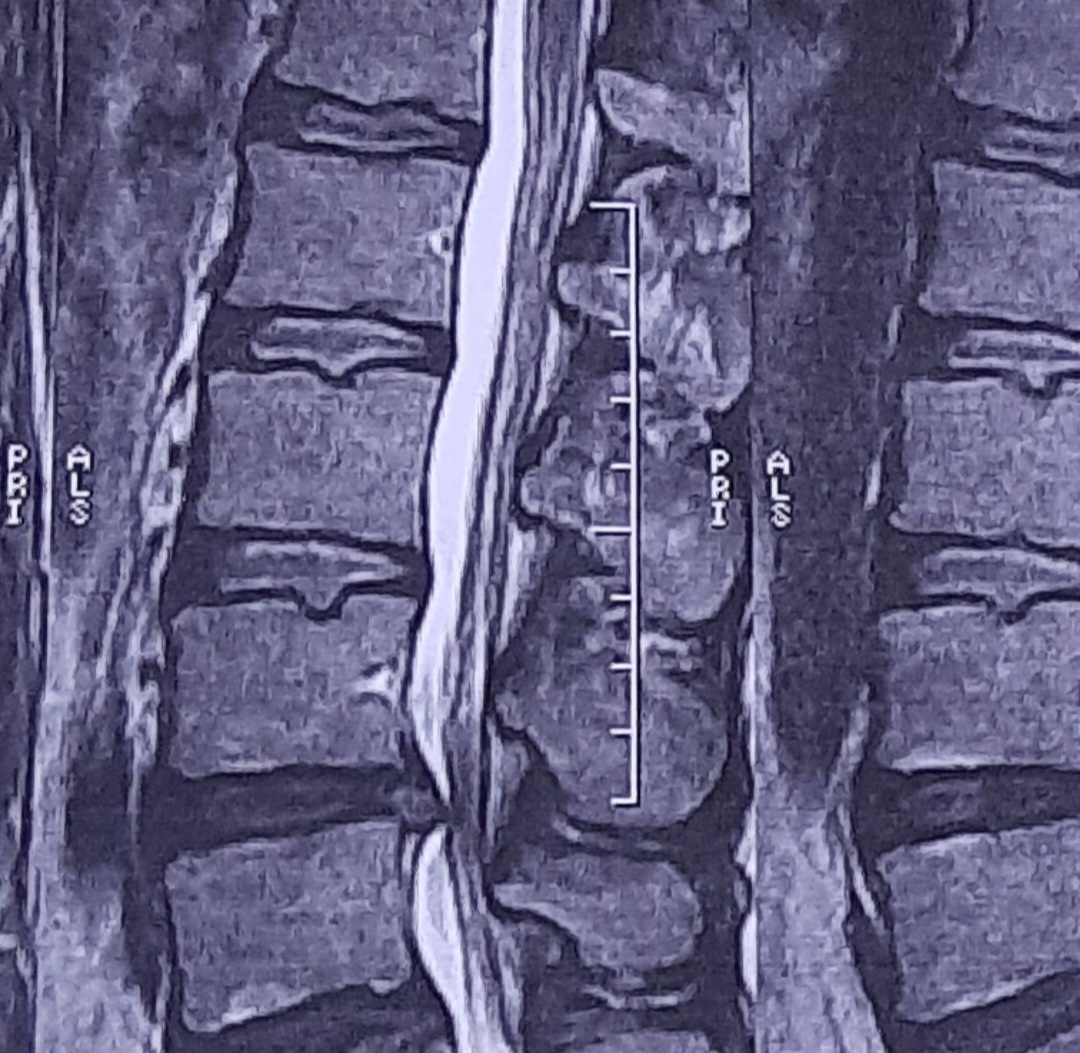

اینم عکس ام آر آی من